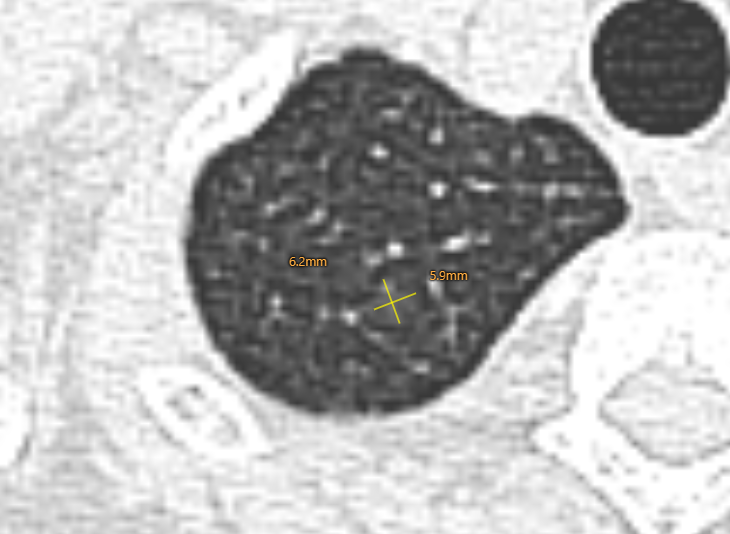

结节2

2013年↓

诊断:这个结节是一个混杂密度结节,大部分以实性成分为主,周边可见毛刺及分析,由于病灶非常小,如果首次发现还是要小心,但是通过以下多次的随访和复查,我们考虑良性纤维灶的概率更高。

但是由于这个结节位于外周带,非常容易切除,因为和主病灶是同侧,所以这个结节,我么可以考虑一次处理掉。